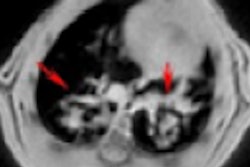

Researchers assigned a lung ultrasound score of 0-3 corresponding with disease severity for 14 unique lung sections. Image courtesy of Umberto Sabatini and the ASA.While the new research focused on the use of lung ultrasound, Sabatini praised ultrasound's other merits, too, especially its use for abdominal imaging. Based on his experience, he thinks the modality will be a staple for physicians long after the pandemic is over.